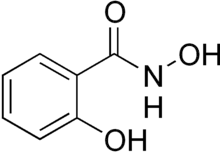

| Preferred IUPAC name

N,2-Dihydroxybenzamide | |

2-Hydroxybenzenecarbohydroxamic acid | |

| C7H7NO3 | |

| Molar mass | 153.137 g·mol−1 |

| Appearance | Brownish crystalline powder |

| Melting point | 175 to 178 °C (347 to 352 °F; 448 to 451 K) |

Salicylhydroxamic acid (SHA or SHAM) is a drug that is a potent and irreversible enzyme inhibitor of the urease enzyme in various bacteria and plants; it is usually used for urinary tract infections. The molecule is similar to urea but is not hydrolyzable by urease;[1] it thus disrupts the bacteria's metabolism through competitive inhibition. It is also a trypanocidal agent. When administered orally, it is metabolized to salicylamide, which exerts analgesic, antipyretic, and anti-inflammatory effects.